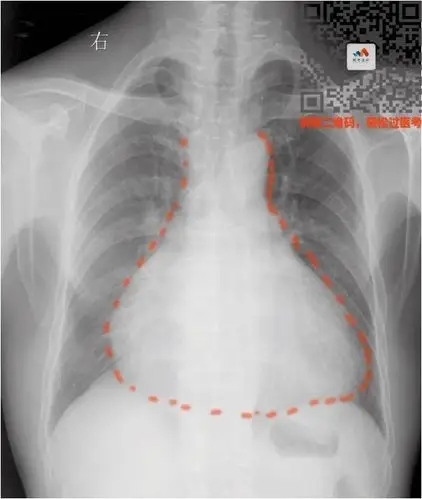

靴型心

要么是心脏本身增大(心包积液—烧瓶心)要么是心包里面灌了水普大型